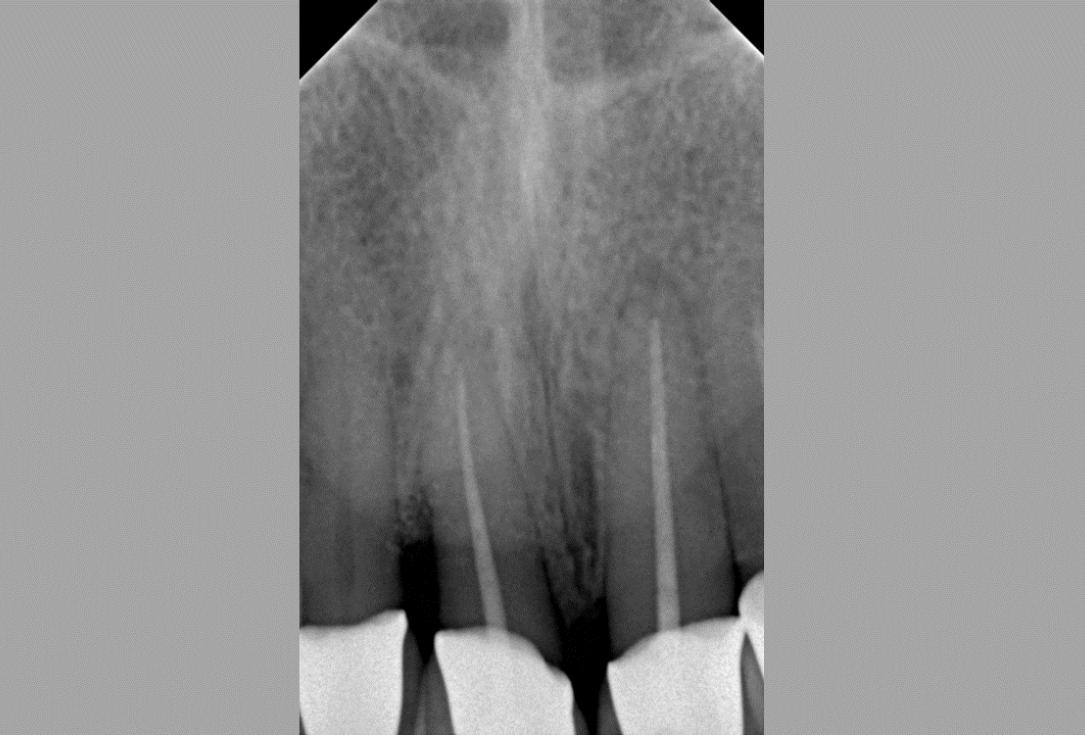

02/08 - Pre-operative radiograph of the defect reveals a deep intrabony defect on tooth 11.Non-contained intrabony defect treated with the simplified papilla preservation flap in conjunction with Straumann® Emdogain® and a particulate bone grafting material - Prof. Dr. Dr. A. Kasaj